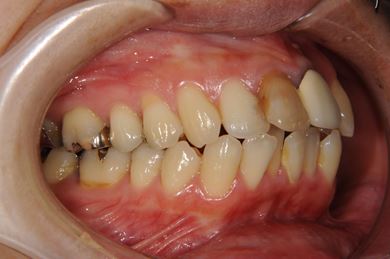

全顎矯正治療+セラミック治療

| 性別/年齢 | 女性 / 35歳 | ||||||||||||||||||||||||||||||||

| 主訴 | 出っ歯 上顎前歯の並び | ||||||||||||||||||||||||||||||||

| 治療方針 | 上下歯牙がだいぶ前にでていて口が閉じづらい状態でした。なるべく金属が入っている歯を抜歯したいので、上下左右第二小臼歯を抜歯して、その隙間を利用して、口元をさげていきました。また、口元を最善の状態にうるために、抜歯スペースを使用したあと、上下左右のインプラントアンカー(釘)でより一層口元を後ろにさげていきました。ただの抜歯ケースよりだいぶ口元が下がっているのが分かります。抜歯したスペースががたつき(叢生量)で使用してしまう場合には、このような方法でより口元をさげることができます。お顔立ちがとてもよくなりました。とても協力していただけたので、しっかりと良くなることができました。 | ||||||||||||||||||||||||||||||||

| 治療内容 | 唇側矯正(ホワイト・上下左右第二小臼歯抜歯・上下インプラントアンカー)、オールセラミッククラウン1本(オールセラミック用土台1本)、ジルコニアフレームオールセラミッククラウン1本 | ||||||||||||||||||||||||||||||||